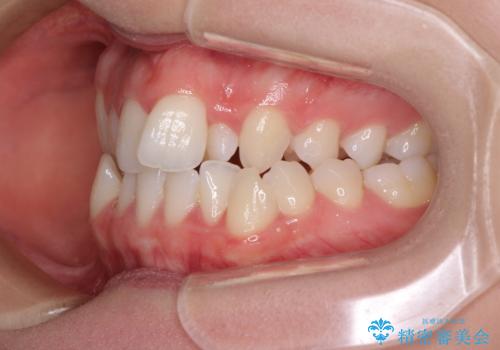

上顎骨の横幅が狭く、奥歯は上顎よりも下顎が外側にある咬合状態でした。

急速拡大装置により骨格はある程度改善されましたが、奥歯の咬み合わせ改善に非常に時間がかかってしまいました。

デコボコを改善させるだけでなく、しっかりとした咬合状態を獲得することができ、患者様には大変満足していただけました。